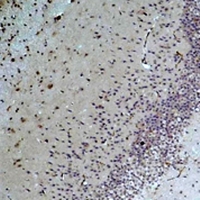

Immunohistochemical analysis of Bestrophin-1 staining in rat brain formalin fixed paraffin embedded tissue section. The section was pre-treated using heat mediated antigen retrieval with sodium citrate buffer (pH 6.0). The section was then incubated with the antibody at room temperature and detected using an HRP conjugated compact polymer system. DAB was used as the chromogen. The section was then counterstained with haematoxylin and mounted with DPX.